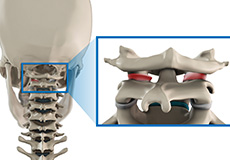

Spondylolysis

Spondylolysis is a stress fracture in the vertebra that may progress into spondylolisthesis, a condition where the vertebra gets displaced from the spinal column. Spondylolysis is the cause of frequent low back pain in children. It is more common among children and teenagers who participate actively in sports such as football, weightlifting, and gymnastics.